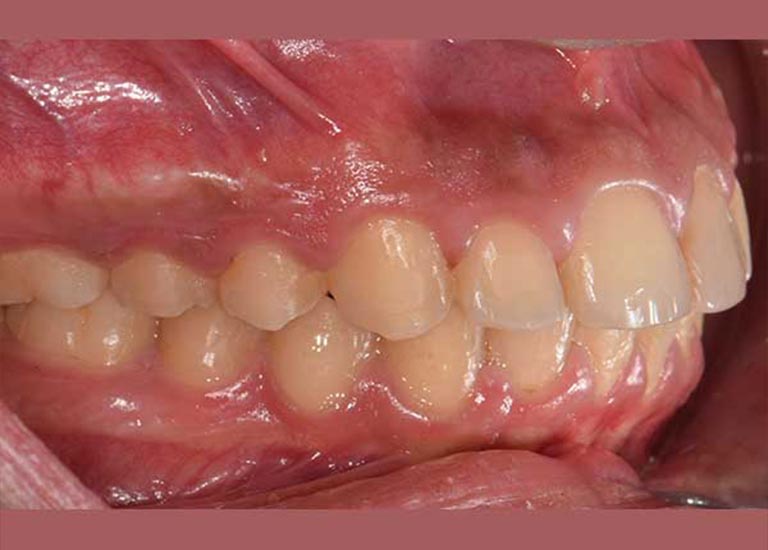

This little kid was suffering from severe protrusion (there was a space between the upper and lower front teeth), and regression in the lower jaw.

The condition was treated by fixed orthodontics and a functional device that serves to advance the lower teeth and the bearing bone forward and stimulate the advancement of the lower jaw forward and Put the upper teeth back.

The case was successfully treated without tooth extraction, as is usual in some similar cases.